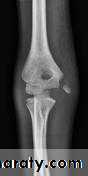

Intercondylar fracture of humerus:

Lateral condyle fracture of humerus:

Medial condyle fracture of humerus: